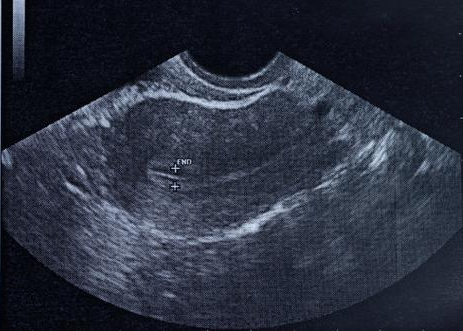

术后1-2周复查超声,评估子宫恢复情况,及时发现残留或感染。